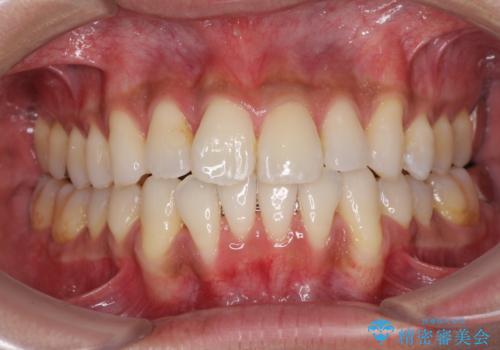

- 上下前歯の叢生を気にして来院された患者様です。

奥歯はクロスバイトとなっているので上顎は側方拡大を行いつつ、上下全体の叢生をインビザラインにより改善することとしました。

治療途中でクリーニングやホワイトニングを行い、歯列が整うと同時に明るい口元となりました。